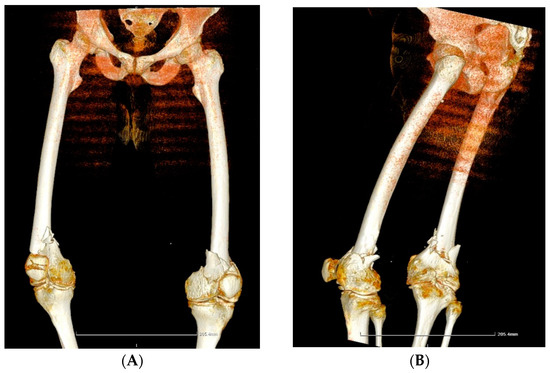

Case 2. A 39-year-old patient with severe haemophilia A, haemophilic arthropathies, and chronic viral hepatitis C, but no other comorbidities, was brought to the Emergency Unit after a car accident with acute pain and complete functional impotence of both legs. Upon examination, it was found that the patient had a bilateral femoral supracondylar fracture (Figure 2A,B). The patient underwent surgical intervention, specifically an open reduction and osteosynthesis with plates and screws on both legs (Figure 2C,D), while being treated with an extended half-life (EHL) FVIII concentrate to prevent and control bleeding. The total EHL FVIII required for the surgery and recovery was 63,500 IU. After three weeks of hospitalization, the patient’s condition improved, and he was discharged with the following instructions: 8–12 weeks of rest, plaster immobilization for 8–10 weeks, pain medication as needed, X-ray checkup at 4–8 weeks, and monitoring and adjustment of EHL FVIII doses. Bilateral hip-neck or femoral supracondylar fractures are rare, especially in individuals with haemophilia. A comprehensive approach and one-stage surgical intervention are recommended for these debilitating conditions despite the demanding and costly therapy involved. However, appropriate and timely management can help avoid the significantly higher costs associated with staged orthopaedic surgery.

Figure 2.

(A,B) Case 2—Computed tomography image: bilateral femoral supracondylar comminuted fracture. (C,D) Case 2—X-ray of right and left femur and knee. Open post-reduction status and internal fixation with present osteosynthesis material (plate with screws) at the level of the diaphysis and distal femoral epiphysis, following a femoral supracondylar comminuted fracture.